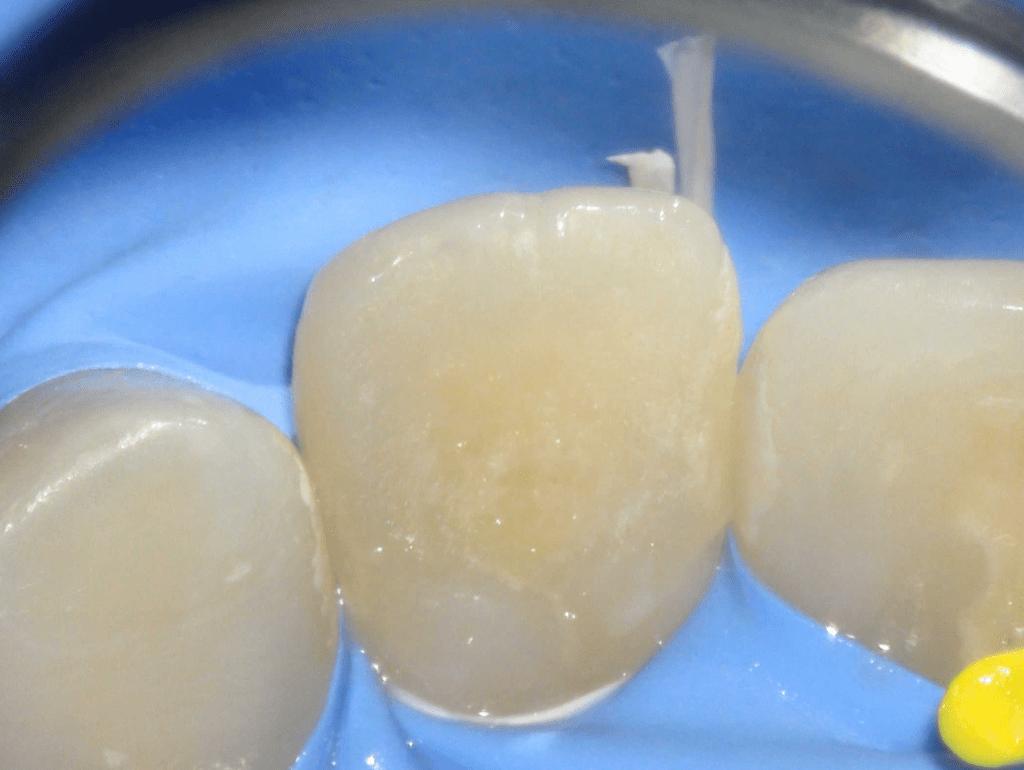

Fractura con exposición pulgar

Reconstrucción con recubrimiento pulgar indirecto